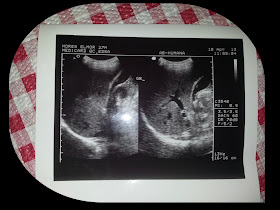

ULTRASOUND RESULT ON WHOLE ABDOMEN